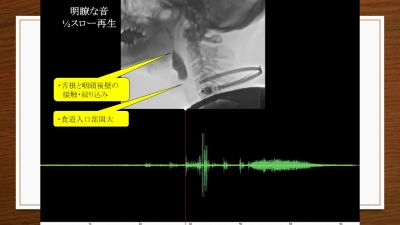

3、頸部聴診法の基本と5つの異常音を学ぶ

4、頸部聴診法習得のコツ

●頸部聴診と視診・触診で総合的に嚥下状態をイメージする